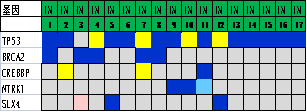

通过进一步基因表达谱测序���,对组织形态学和免疫组化水平界定的TNBC亚型的基因变异情况进行分析����,筛选各亚组之间的差异表达基因及表达意义探究��,结果显示���:1.免疫治疗相关的生物标记物MSI-H��、TMB-H����,作为一个低频发生事件����,在TNBC中不太可能常规作为免疫治疗有效性的评估手段��;TNBC的MSI发生机制可能与结直肠癌不同����、突变热点不同��。2. 整个研究队列中基因表达存在明显差异��,充分显示了患者个体间差异的存在����,从分子水平揭示了TNBC是一种高度异质性肿瘤��。3. TP53基因变异率发生最高��,提示在TNBC形成中可能扮演非常重要的角色����。4. TNBC分型的基因表达聚类分析方面存在差异(图2)����,这些差异基因参与了多种不同的生物学通路��,筛选特异的分子标记物或靶向治疗的靶点以期指导临床治疗���。

图2. 基于组织形态学及免疫组织化学标记物的TNBC亚型的基因表达聚类分析